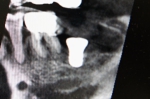

前歯部インプラント骨移植同時症例

大学病院よりご依頼いただいた症例。仮歯が入っていますが、欠損部歯茎が大きくへこんでいて、CT画像ではパノラマレントゲンで想定していたよりもかなり大きく骨がなかったですが、インプラント手術と骨の移植を同時に行い審美的にも回復しました。また同時に行うことにより治療期間が9か月→4か月の短縮されました。被せ物には審美性を考慮して土台からセラミックを使用しました。